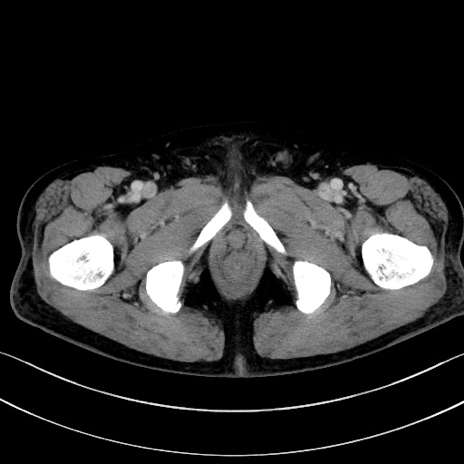

症例15(横断像)

【症例】70歳代男性

【主訴】腹痛

【現病歴】今朝から腹痛あり。全体的に痛い。特に左上の方。排ガスが今日はない。冷や汗が出る。

【既往歴】直腸癌術後

【身体所見】左側腹部〜上腹部に圧痛あり。腹膜刺激症状明らかなではない。軽度反跳痛。左下腹部に術後瘢痕あり。

【データ】WBC 7700、CRP 0.02